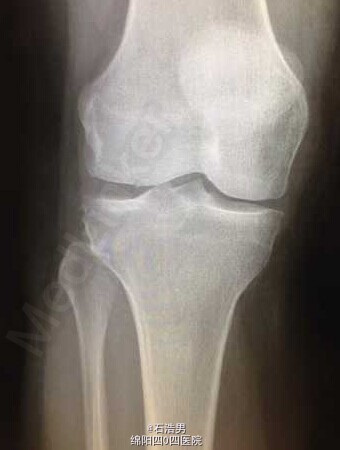

特殊断裂一例

患者,40岁,从7米高的梯子摔倒。此前并无任何受伤。我从来没有见过这个特殊的断裂,分享给大家